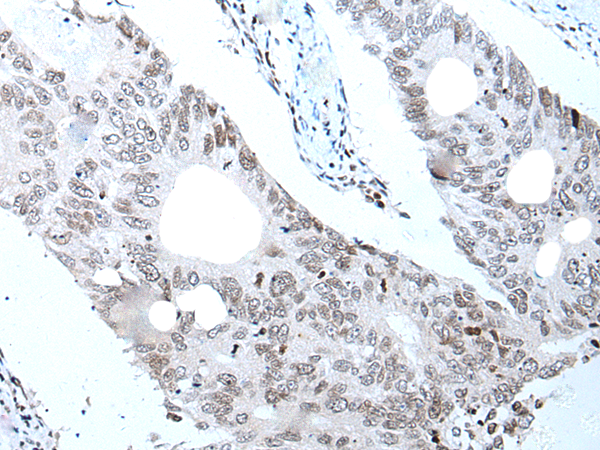

分类: 科研抗体货号: P12874别名: AND1; CTF4; AND-1; CHTF4应用: IHC反应种属: Human